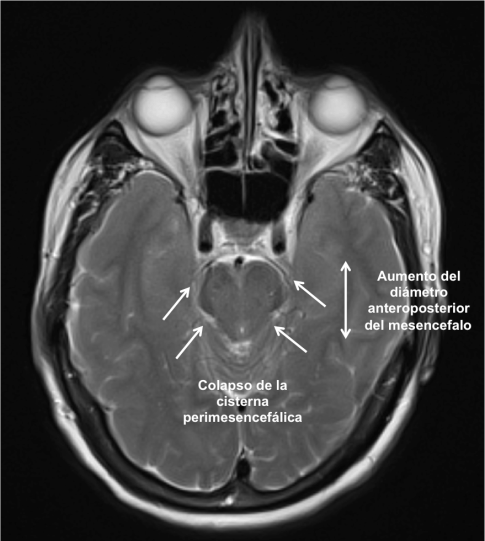

En la Imagen 3, el descenso del cerebro produce un colapso de las cisternas basales y un aumento del diámetro anteroposterior del mesencéfalo.